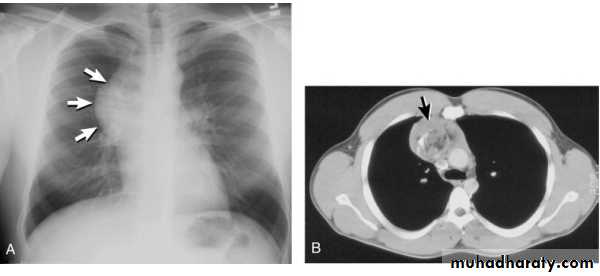

Tension pneumothorax.

On a posteroanterior chest x-ray (A), the left hemithorax is very dark or lucent because the left lung has collapsed completely (white arrows).

The tension pneumothorax can be identified because the mediastinal contents, including the heart, are shifted toward the right, and the left hemidiaphragm is flattened and depressed. A computed tomography scan done on a different patient with a tension pneumothorax (B) shows a completely collapsed right lung (arrows) and shift of the mediastinal contents to the left.

chest practice

Tension Pneumothorax. Portable chest film in a 43-year-old woman with ARDS shows a large right pneumothorax with mediastinal shift and ipsilateral diaphragmatic depression, suggesting tension.

Air was evacuated under pressure during emergent placement of a right chest tube.